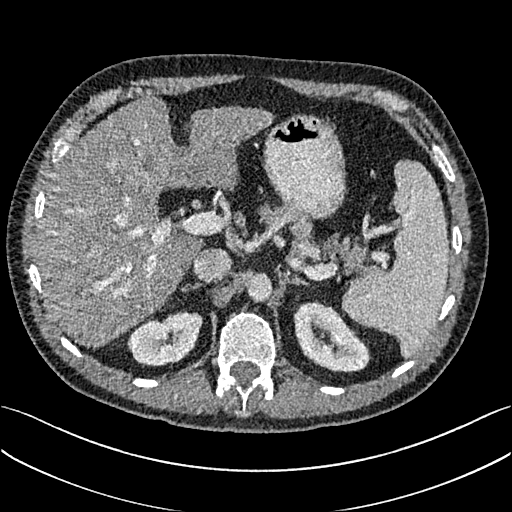

To demonstrate the effectiveness of the proposed network, we perform the qualitative comparisons over three representative abdominal images presented in Figs. 3, 5 and 7. For better evaluations of the image quality with different denoising models, zoomed regions-of-interest (ROIs) are marked by red rectangles and shown in Figs. 4, 6 and 8 respectively. Note that all results from different denoising models focus on two aspects: content restoration and noise-reduction. All CT images in axial view are displayed in the angiography window [-160, 240]HU.

The real NDCT images and corresponding LDCT images are presented in Figs. 3a and 3b. As observed, there are distinctions between ground truth (NDCT) images and LDCT images. Figs. 3a and 7a show the lesions/metastasis. Fig. 5a presents focal fatty sparing/focal fat. In Figs. 4a, 6a and 8a, these lesions can be clearly observed in NDCT images; in contrast, from Figs. 4b, 6b, and 8b, it can be seen that the original LDCT image is noisy, and lacks structural features for task-based clinical diagnosis. All adopted denoising models suppress noise to some extent.

Mean-based methods can effectively reduce noise, but the side effect is impaired image contents. In Fig. 3c, -net greatly suppresses the noise, but blurs some crucial structural information in the porta hepatis region. Meanwhile, some waxy artifacts can still be observed in Fig. 6c. -net does not produce good visual quality because it assumes that the noise is independent of local characteristics of the images. Even though it retains high SNR, its results are not clinically preferable. Compared with -net, in Figs. 3d and 5d, it can been seen that -net encourages less blurring and preserves more structural information. However, as observed in Fig. 4d, it still over-smooths some anatomical details. Meanwhile, in Fig. 6d, there are some blocky effects marked by the blue arrow. The results obtained by RED-CNN [35] deliver high SNR but blur the vessel details as shown in Figs. 4i and 6i.

For SL-based methods, as observed in Figs. 3e and 5e, SL-net generates images with higher contrast resolution and preserves texture of real NDCT images better than -net and -net. However, Figs. 4e and 6e show that SL-net does not preserve the structural features well, and there still remain small streak artifacts. Subsequently, in Figs. 4e and 4f, SL-net and MSL-net have low frequency image intensity variance because SSIM/MS-SSIM is insensitive to uniform biases [49, 51]. On the other hand, -net preserves the overall image intensity, but it does not preserve high contrast resolution well as SL-net and MSL-net do.

To evaluate the effectiveness of our proposed objective function, we compare our method with existing WGAN-based networks, including WGAN and WGAN-VGG. Considering the importance of clinical image quality and specific structural features for medical diagnosis, we adopted the adversarial learning method [41, 42] in our experiments because WGAN could help to capture more structural information. Nevertheless, based on our prior experience, utilizing WGAN alone may yield stronger noise than other selected approaches, because it only maps the data distribution from LDCT to NDCT without consideration of local voxel intensity and structural correlations. The observations demonstrate that the noise texture is coarse in the images, as shown in Fig. 4g and Fig. 8g, which support our intuition.

Indeed, the images of WGAN-VGG[37], as shown in Fig. 3j, exhibit better visual quality with respect to more details and share structural details similar to NDCT images according to human perceptual evaluations. However, Figs. 4j (marked by the red circle) and 6j (marked by the green circle) suggest that it may severely distort the original structural information. A possible reason is that the VGG network [47] is a pre-trained deep CNN network based on natural images, and the structural information and contents of natural images are different from medical images.

Compared with WGAN and WGAN-VGG, our proposed SMGAN-3D, as shown in Figs. 4l (marked by the red circle) and 6l (marked by the green circle), can more clearly visualize the metastasis and better preserve of the portal vein.

III-D3 Comparison with Image space denoising

To validate the robustness of DL-based methods, we compared our method with the image space denoising method. Figs. 4h and 6h show that BM3D blurs the low-contrast lesion marked by the red circle and smooths specific features marked by the blue arrow. In contrast, SMGAN-3D exhibits better on the low-contrast lesion and yields sharper features as shown in Figs. 4l and 6l.

III-D4 Comparison with 2D-based SMGAN network

In order to evaluate the 3D structural information, we compared SMGAN-3D with SMGAN-2D. As shown in Fig. 4l, our proposed SMGAN-3D generated the results with better subtle details than SMGAN-2D and enjoys more similar statistical noise properties to the corresponding NDCT images. The reasons why SMGAN-3D outperforms SMGAN-2D are follows. First, SMGAN-3D incorporates 3D structural information to improve image quality. Second, SMGAN-2D takes input slice by slice, thus potentially leading to the loss of spatial correlation between adjacent slices.